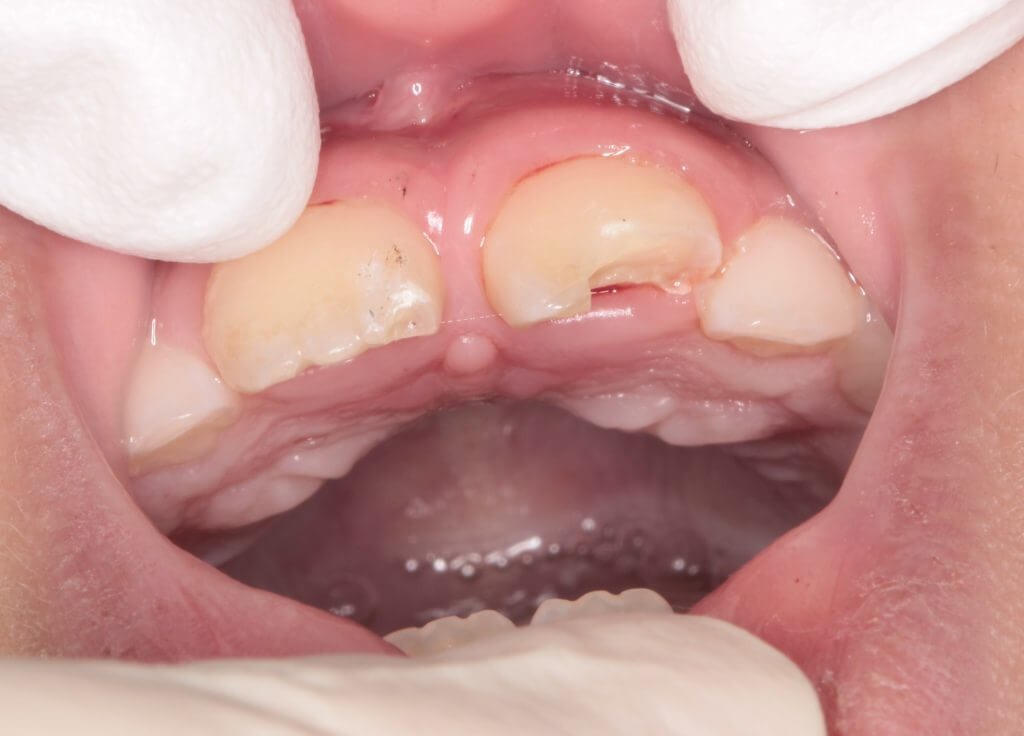

朝、子供が学校への登校中に前歯を強打したということで来院

お母さんが心配されて来院されました。

歯牙の破折は右側と左側に認められます。

口腔内所見では露髄は認められず臨床症状もないため神経には問題はなさそうでした。レントゲン所見でも問題なかったので修復処置に移ります。今回は左側の大きく欠けた歯の一部をお母さんが探して持ってきていたので、それをコンポジットレジンで接着して修復の一部に再利用することとしました。